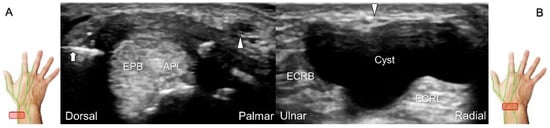

Cheiralgia paresthetica, also known as Wartenberg’s syndrome, is the compressive neuropathy of the superficial radial nerve. Symptoms such as tenderness, numbness, and allodynia can be exacerbated by wrist flexion and ulnar deviation. The nerve can be compressed by a handcuff, watch, bracelet, metal implant, ganglion cyst, or distal radius fracture. Nerve entrapment commonly takes place at the proximal intersection zone pertaining to the first and second extensor compartments (Figure 22).

Additionally, acupuncture and cannulation of the cephalic vein over the distal forearm can lead to nerve injury. To prevent iatrogenic injury, the superficial radial nerve before injection should also be recognized for de Quervain’s syndrome (Figure 23A) [44], ganglion cyst aspiration (Figure 23B), and catheterization (Figure 24A–C). For injection of the superficial radial nerve, an in-plane approach in the nerve’s short axis is preferred (Figure 24D).

Figure 25. Sonographic images depict the location of a neuroma of the superficial radial nerve. The normal/proximal segment (A) and the neuroma in short-axis (B) and long-axis (C) views are seen. White arrowhead: superficial radial nerve; black arrowheads: neuroma; APL: abductor pollicis longus tendon; EPB: extensor pollicis brevis tendon; ECRL: extensor carpi radialis longus tendon; C: cephalic vein.

Figure 22. Sonographic imaging (short-axis view) of the dorsolateral branch of the superficial radial nerve at normal (A), swollen (B), and compressed (C) segments. White arrowhead: normal segment; black arrowhead: swollen segment; orange arrowhead: entrapped segment. ECRL: extensor carpi radialis longus tendon; ECRB: extensor carpi radialis brevis tendon; EPL: extensor pollicis longus tendon.

Figure 23. Sonographic imaging of the superficial radial nerve beside the first extensor compartment of the wrist (A), and a ganglion cyst over the second extensor compartment of the wrist (B). White arrowheads: superficial radial nerve; white arrow: needle. APL: abductor pollicis longus tendon; EPB: extensor pollicis brevis tendon; ECRL: extensor carpi radialis longus tendon; ECRB: extensor carpi radialis brevis tendon.